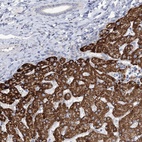

Immunohistochemical staining of human liver shows strong cytoplasmic positivity in hepatocytes.